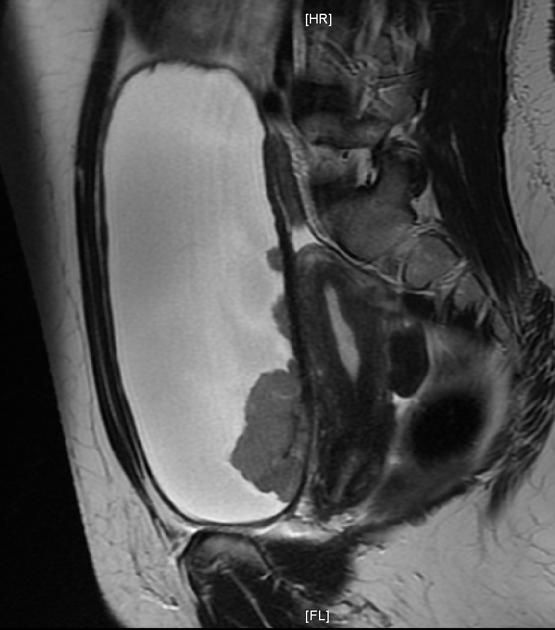

Пациенты часто задаются вопросом, что можно увидеть на МРТ малого таза и какие преимущества у данного метода? Вас могут беспокоить боли в области таза, зачастую это первые признаки серьёзных заболеваний. В этом отделе у человека расположен мочевой пузырь, женские репродуктивные органы и мужские половые органы, лимфатические узлы и кости таза. О причинах и симптомах мы расскажем чуть позже, ну а сейчас остановимся на МРТ исследовании. Что это за процедура и почему она важна для пациента? Магнитно-резонансная томография малого таза это детализированное изображение органов, тканей и крестца на снимке. Процедура необходима для тщательного и качественного обследования внутренних органов малого таза. МРТ позволяет получить информацию о структурных внутренних изменениях в тканях и первичных признаках опасных и серьезных заболеваний. По сравнению с СКТ, на снимках МРТ можно более детально изучить мягкие ткани и всевозможные патологические процессы в них. Вам выписали направление на обследование, но вы не знаете, где делают МРТ органов малого таза? У пациента всегда есть право выбора медучреждения. Сделать правильный выбор клиники и ознакомиться с положительными отзывами, всегда можно при помощи Интернет-ресурсов.

Результаты диагностики

После того, как диагностика закончена, пациент может быть свободен, а доктор-рентгенолог приступает к расшифровке результатов. Расшифровать МРТ малого таза грамотному рентгенологу не представляет труда. На имеющемся трехмерном изображении просматриваются четкие участки самых мельчайших патологических процессов, образований, просматриваются четкие границы и представляется возможность определить природу происхождений имеющихся новообразований, а также оценить состояние сосудов, лимфатических узлов и костной системы этой области. Всё это доктор-рентгенолог описывает в заключении к МРТ органов малого таза. По времени этот этап длится от 2 до 24 часов.

Снимки МРТ малого таза, записанные на диск и заключение рентгенолога передаётся пациенту для его лечащего врача. На основании этого заключительного диагноза, лечащий врач назначает пациенту необходимое лечение или принимает решение о целесообразности проведения оперативного вмешательства. По желанию или по требованию доктора, снимки можно распечатать.

Какие патологии выявляет МРТ малого таза?

Динамическое контрастное усиление дополняет диагностический ряд уникальной информацией – о химических и физических процессах в органах. Магнитно-резонансная томография применяется для выявления небольших патологических образований диаметром в несколько миллиметров на начальных стадиях (опухоли), определения сосудистых аномалий, нарушений микроциркуляции.

Нельзя ответить однозначно, какой метод исследования органов малого таза лучше. Есть много разных клинических ситуаций, при которых достоверностью обладает один из описанных методов или требуется комбинированное использование инструментальных способов. МРТ лучше визуализирует ткани, сосуды, а КТ хорошо показывает костные структуры.

Суть компьютерной или магнитно-резонансной томографии – послойное сканирование тела с получением срезов через определенное количество миллиметров. Только при КТ используется рентгеновское излучение, а при МРТ – магнитный резонанс атомов водорода. Компьютерная томография доставляет больше вреда организму из-за лучевого воздействия на здоровые ткани, поэтому часто делать нельзя.